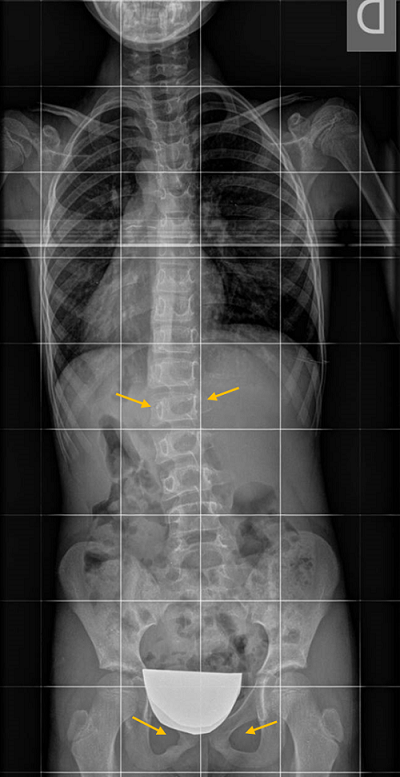

Una curva larga de toda la columna vertebral dirigida hacia el hombro que se ve más caído indica que el paciente se inclinó armónicamente hacia ese lado (Figura 5). Asimismo, una curva dirigida hacia la pelvis que se eleva, o hacia el miembro que se apoya menos, posiblemente son posicionales.

Figura 5. Escoliosis posicional. Inclinación del hombro hacia el lado más bajo. La columna vertebral se curva hacia el hombro que se ve más caído, indica que el paciente se inclinó armónicamente hacia ese lado. Mostrar/ocultar

En las dismetrías, el paciente caerá hacia el lado más bajo, como mencionamos sobre la Figura 5, pero para compensar este desequilibrio la columna puede inclinarse hacia el lado más alto, bajando el hombro de ese lado. Estas curvas son lógicas y no son escoliosis. Sin embargo, podemos encontrarnos con situaciones contradictorias o mixtas (Figura 6).

Figura 6. Escoliosis posicional. Dismetría de miembros inferiores: la columna vertebral se inclina hacia el lado más alto y además eleva el hombro del mismo lado. Es una situación mecánicamente ilógica, debida a posiciones que adoptan los pacientes en el momento de hacer la radiografía. . Mostrar/ocultar